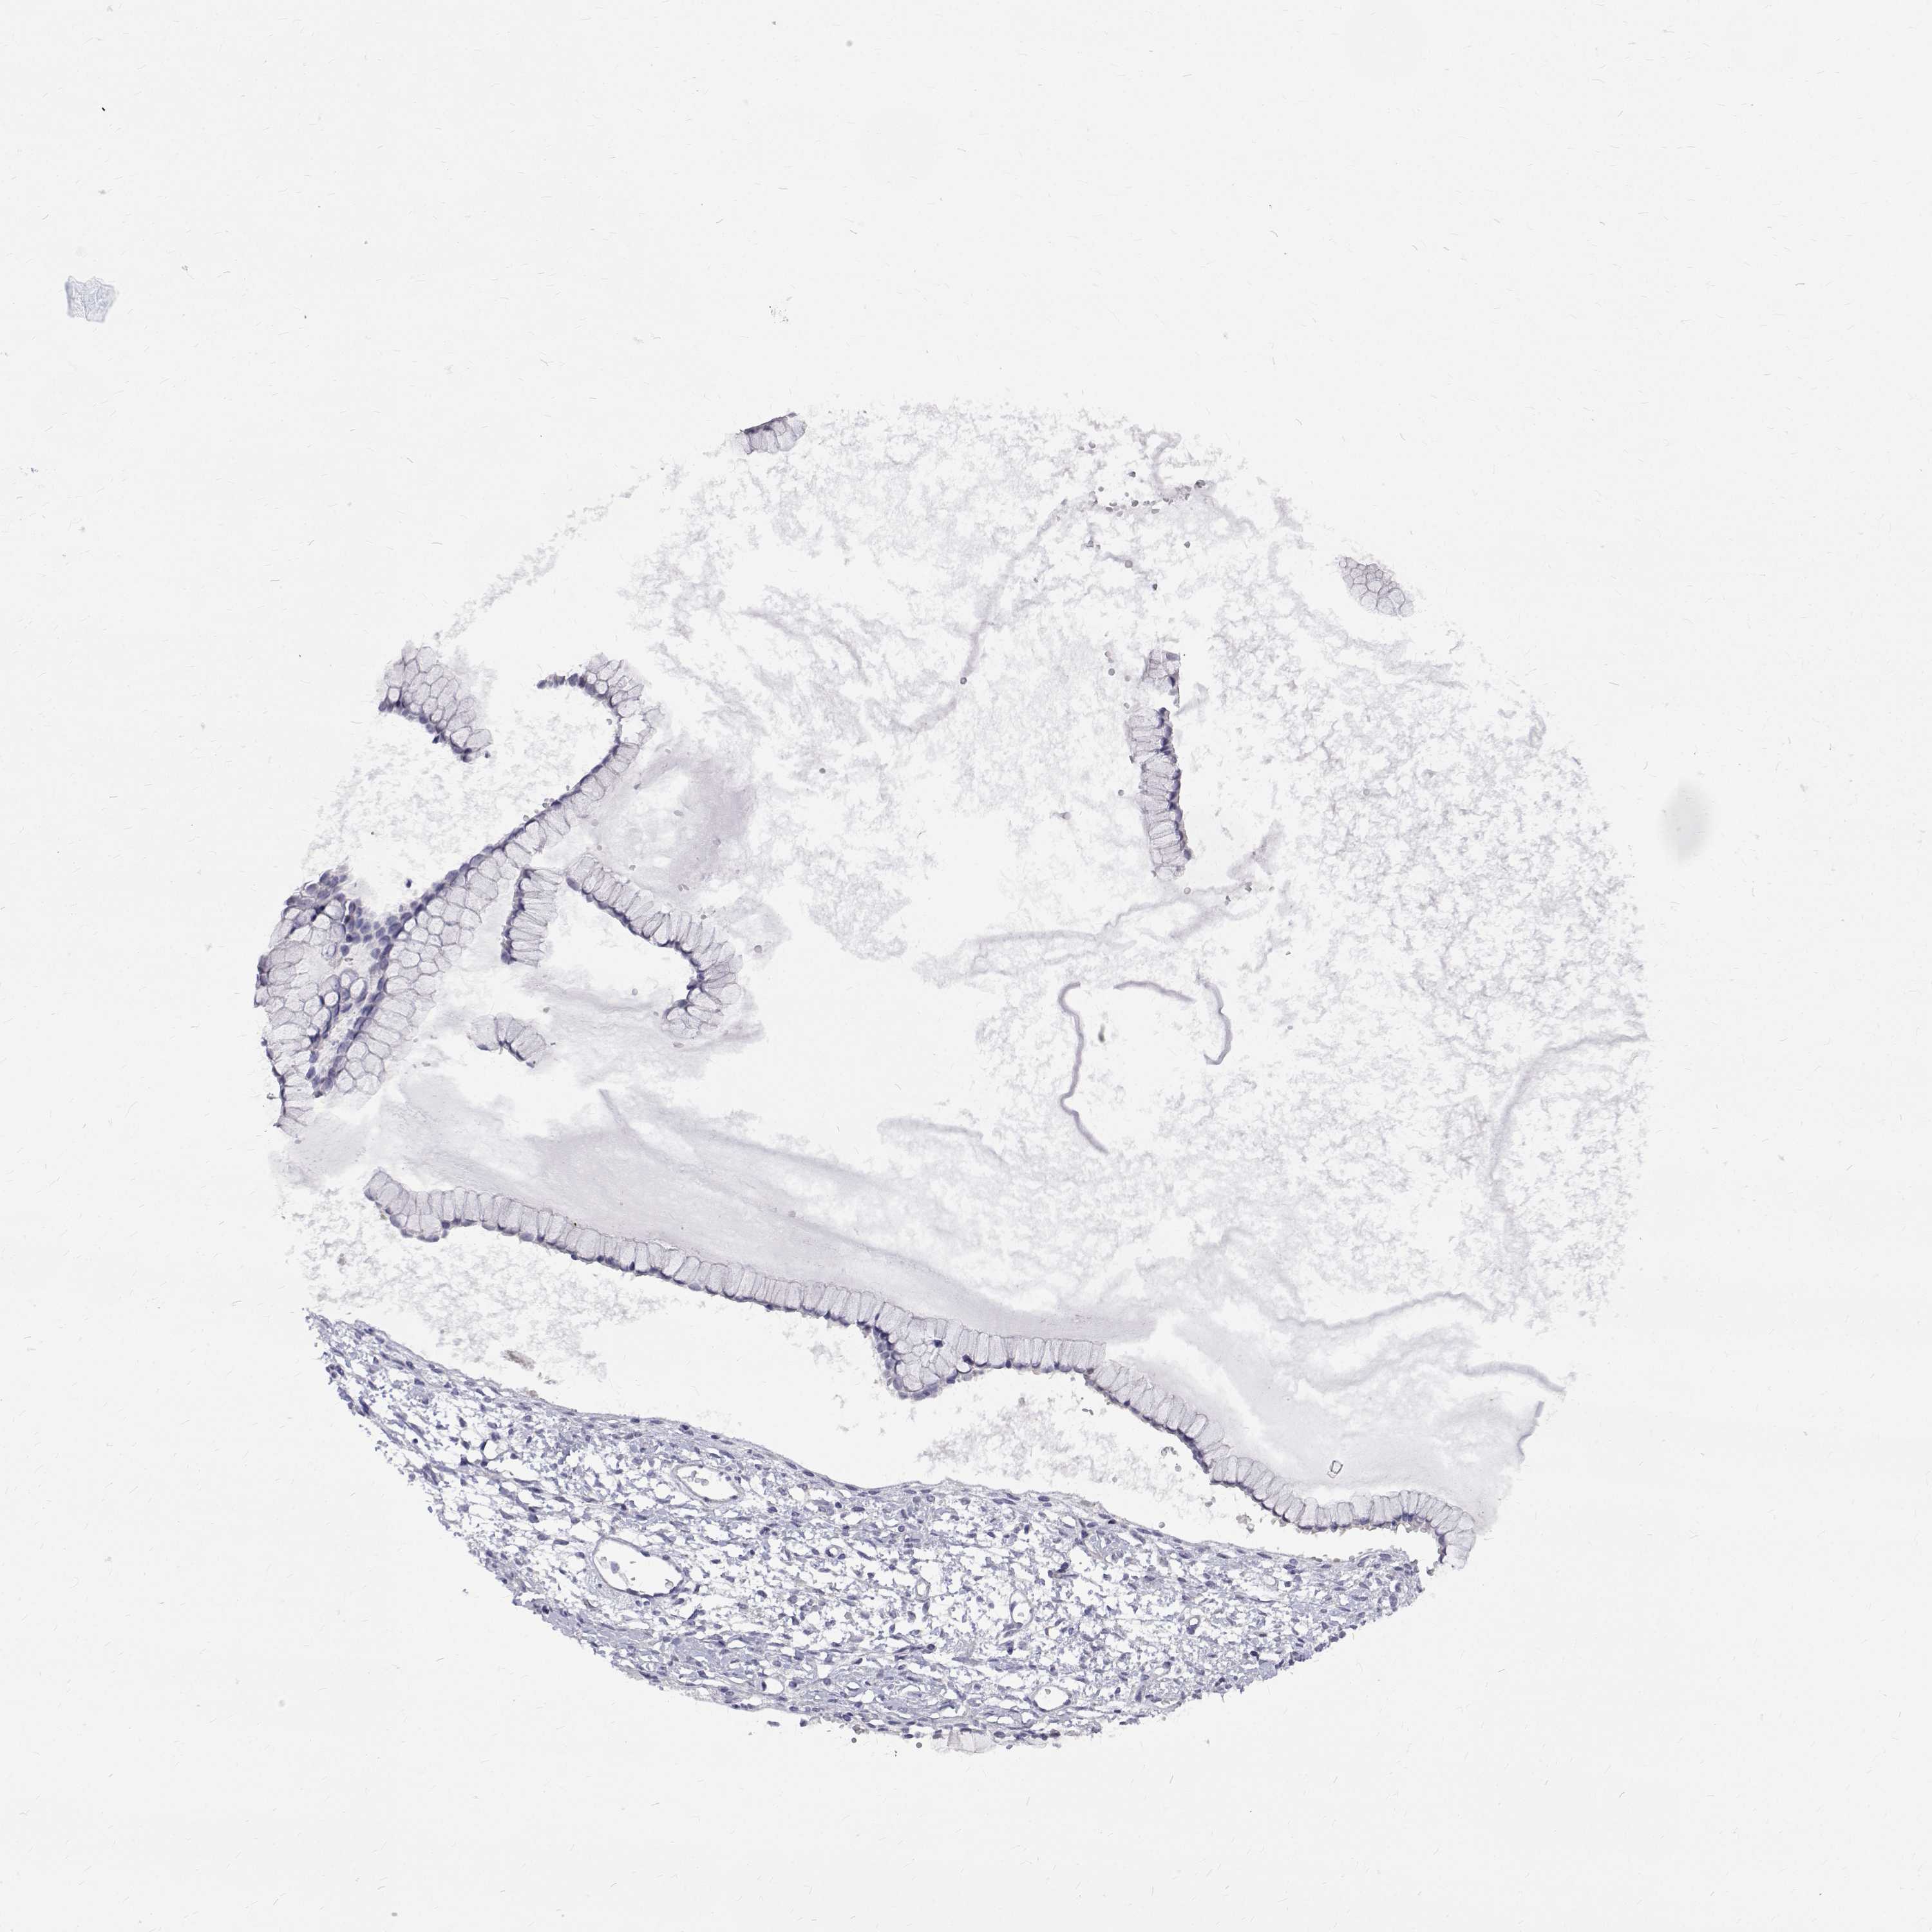

OVARIAN CANCER - Protein expressioni

A mouse-over function shows sample information and annotation data. Click on an image to view it in a full screen mode. Samples can be filtered based on level of antibody staining by selecting one or several of the following categories: high, medium, low and not detected. The assay and annotation is described here.

Note that samples used for immunohistochemistry by the Human Protein Atlas do not correspond to samples in the TCGA dataset.

Antibody stainingi

Antibody staining in the annotated cell types in the current human tissue is reported as not detected, low, medium, or high, based on conventional immunohistochemistry profiling in selected tissues. This score is based on the combination of the staining intensity and fraction of stained cells.

Each image is clickable and will lead to virtual microscopy that enables deeper exploration of all samples and also displays staining intensity scores, fraction scores and subcellular localization as well as patient and tissue information for each sample.

Antibody HPA062294

Staining

High

Medium

Low

Not detected

Intensity

Strong

Moderate

Weak

Negative

Quantity

>75%

75%-25%

<25%

None

Location

Nuclear

Cytoplasmic/membranous

Cytoplasmic/membranous,nuclear

Cystadenocarcinoma, serous, NOS

Cystadenocarcinoma, mucinous, NOS

Carcinoma, endometroid